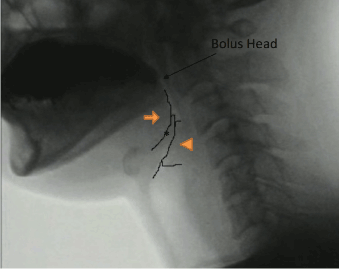

From the viewpoint of the neoglottis morphology, prior to swallowing initiation, the arytenoid cartilages sit on the cricoid cartilage and are already located in an elevated position due to the pexis procedure. Furthermore, in the case of post-SCL swallow, we frequently found that the valleculae were not easily identifiable due to epiglottic approximation to the root of the tongue. These features appeared to make it easier for the arytenoid to make contact with the tongue base (Figure 3). Thus, by the time the bolus has arrived at the PES, the tongue base (attached to the epiglottis) is seen to approximate the arytenoids effectively and rapidly to close the supraglottic passage (Figure 4). Moreover, the supraglottic airway remains closed until after the PES has opened (Figure 5). These findings, which are consistent with the report by Woisard et al. [17], were demonstrated by the prolonged duration of airway closure and PES opening.

Figure 5. Retrofluorographic lateral view at the passage of the bolus tail at the PES, showing that the airway is still closed